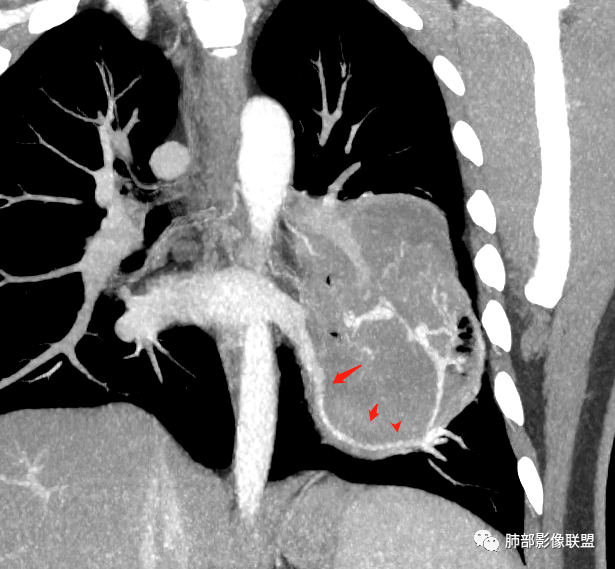

下叶基底干支气管受压下移

下叶背段支气管受压稍后内移位,通畅

就是支气管目前基本没有堵塞,只是受压

下肺静脉:

还是肺动脉供血,肺静脉引流

青年男性,体检发现左肺不规则类圆形占位性病变,叶间裂区域,定位胸膜来源。左肺下叶支气管受压狭窄,但管壁光整,未见腔内阻塞或管壁受侵。包块边界清晰,浅分叶,内部密度不均匀,病灶后份见空气新月征。渐进性强化,增强动脉期见分支状血管,蛇纹血管征。肺门纵膈未见增大淋巴结,符合孤立性纤维瘤(SFT)。

5)肿瘤的强化程度及方式:增强扫描肿瘤早期实性成分呈不均匀斑片或斑驳样强化,亦可呈“ 地图样” 明显强化,强化程度不一,可呈轻度-显著强化;静脉期持续强化,多期增强及动态增强扫描均呈“快进慢出”型强化,且强化范围逐渐增大并趋均匀。肿瘤内部及周围常见多发粗细不等强化或流空肿瘤血管影。瘤体内“蛇纹血管”在其他诸如硬化性肺细胞瘤、错构瘤等等是非常罕见的。